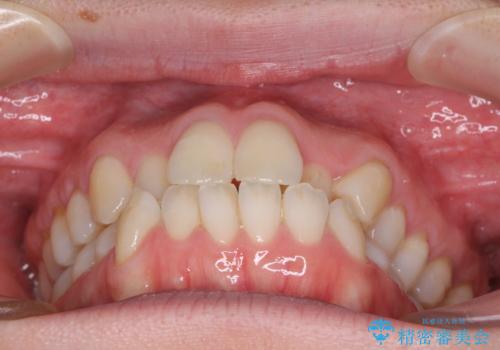

受け口傾向の歯並びをインビザラインで改善

- 受け口傾向でクロスバイトの前歯を治したいとのことで来院された患者様です。

下顎骨が若干左側に変位していたため、右側にアンカースクリューを使用し、積極的に移動させながらインビザラインにて矯正治療を行うこととしました。

インビザラインによる矯正治療は、受け口傾向の治療に非常に適した方法であり、事前にシミュレーションに沿って治療を進めることできます。

今回の治療では骨格的な偏位があったためアンカースクリューを使用し、より確率の高い治療を行うことができました。